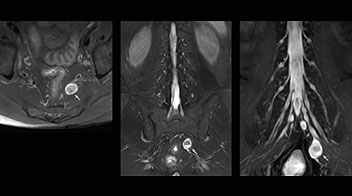

Northern Fukushima Medical Center (NFMC) Imaging Center uses the 3D NerveVIEW sequence for performing MR neurography, particularly in patients with pain and weakness in the lower limb. “It is included in about 20% of the approximately 150 lumbar spine MRI exams each month at NFMC, and can help us to determine if structures are impinging on the nerves,” says Hajime Tanji, RT, MRI technologist at NFMC.

Implementing NerveVIEW without lengthening exam time “The source images of NerveVIEW exhibit a contrast similar to STIR or fat-suppressed T2-weighted images. So, in our neurography exams we are replacing the 2D T2-weighted coronal sequence with 3D NerveVIEW. With this, we add a lot of useful information without adding scan time. This is important for patients with severe lower extremity symptoms, as they often find it difficult to maintain still during the whole MRI examination, so the exam should be as short as possible.” “We have currently implemented 3D NerveVIEW on our Achieva 3.0T dStream MRI system only. Because the 3D NerveVIEW method is based on a background signal suppression technique, we decided to use the high SNR of our 3.0T MRI system for obtaining the best possible visualization of peripheral nerves,” says Tanji. “Where NerveVIEW of the lumbar plexus is currently used as a subroutine scan for patients with strong lower limb symptoms, its use for visualization of the brachial plexus, is currently limited to special cases such as schwannomas and neuritis, usually only 1 or 2 cases per month.”

“NerveVIEW can clearly show nerve courses and presence of nerve compression. However, when multiple abnormalities are seen, it can still be hard to determine which nerve is causing the symptoms,” says Dr. Yabuki. “In our experience so far, we see abnormal findings on NerveVIEW in about 70% of elderly patients. As the pain is usually caused by only one nerve, we thus need to find the exact corresponding nerve.” “With a nerve root block, the patient's pain is improved by infiltration of local anesthesia directly around the nerve root considered to be responsible. Knowing such nerve root block findings prior to image interpretation, helps to easily recognize abnormal findings on NerveVIEW as well. In other words, without a priori knowledge, based on symptoms and/or nerve root block findings, we must be aware of the possibility of overdiagnosis.”

The addition of the nerve-selective NerveVIEW sequence to its spine MRI protocol has given NFMC competitive advantages, according to Tanji. “Since we started including NerveVIEW routinely, the demand for lumbar spine MRI examinations has increased, especially for pre-surgical planning purposes and for patients with chronic lower extremity symptoms,” he says. “Moreover, because no other hospitals in our region are doing nerve plexus imaging yet, we often receive referrals for MR neurography studies from other hospitals even if they have an MRI scanner. Some requests come from as far as 100 km away. NerveVIEW definitely provides us a competitive advantage.” “Based on our experience, we can certainly recommend NerveVIEW to other centers,” Dr. Yabuki adds. “The sequence opens up many possibilities to facilitate the diagnosis of lower extremity pain and to inform our decision-making regarding therapy and surgery.”